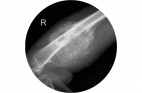

Выявлена зависимость выживаемости собак с остеосаркомой от уровня холестерина